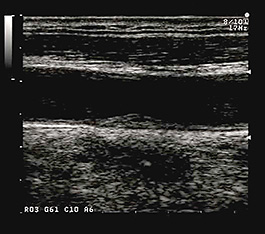

健常高齢者における総頸動脈のIMCである。IMTは1mm程度である。層構造は不明瞭で、その壁面のエコー輝度が上昇している。 |

動脈硬化の進行によりIMTは1.4mmと肥厚を呈している。IMCは不均一で、限局性にエコー輝度の増強部分がみられる。 |